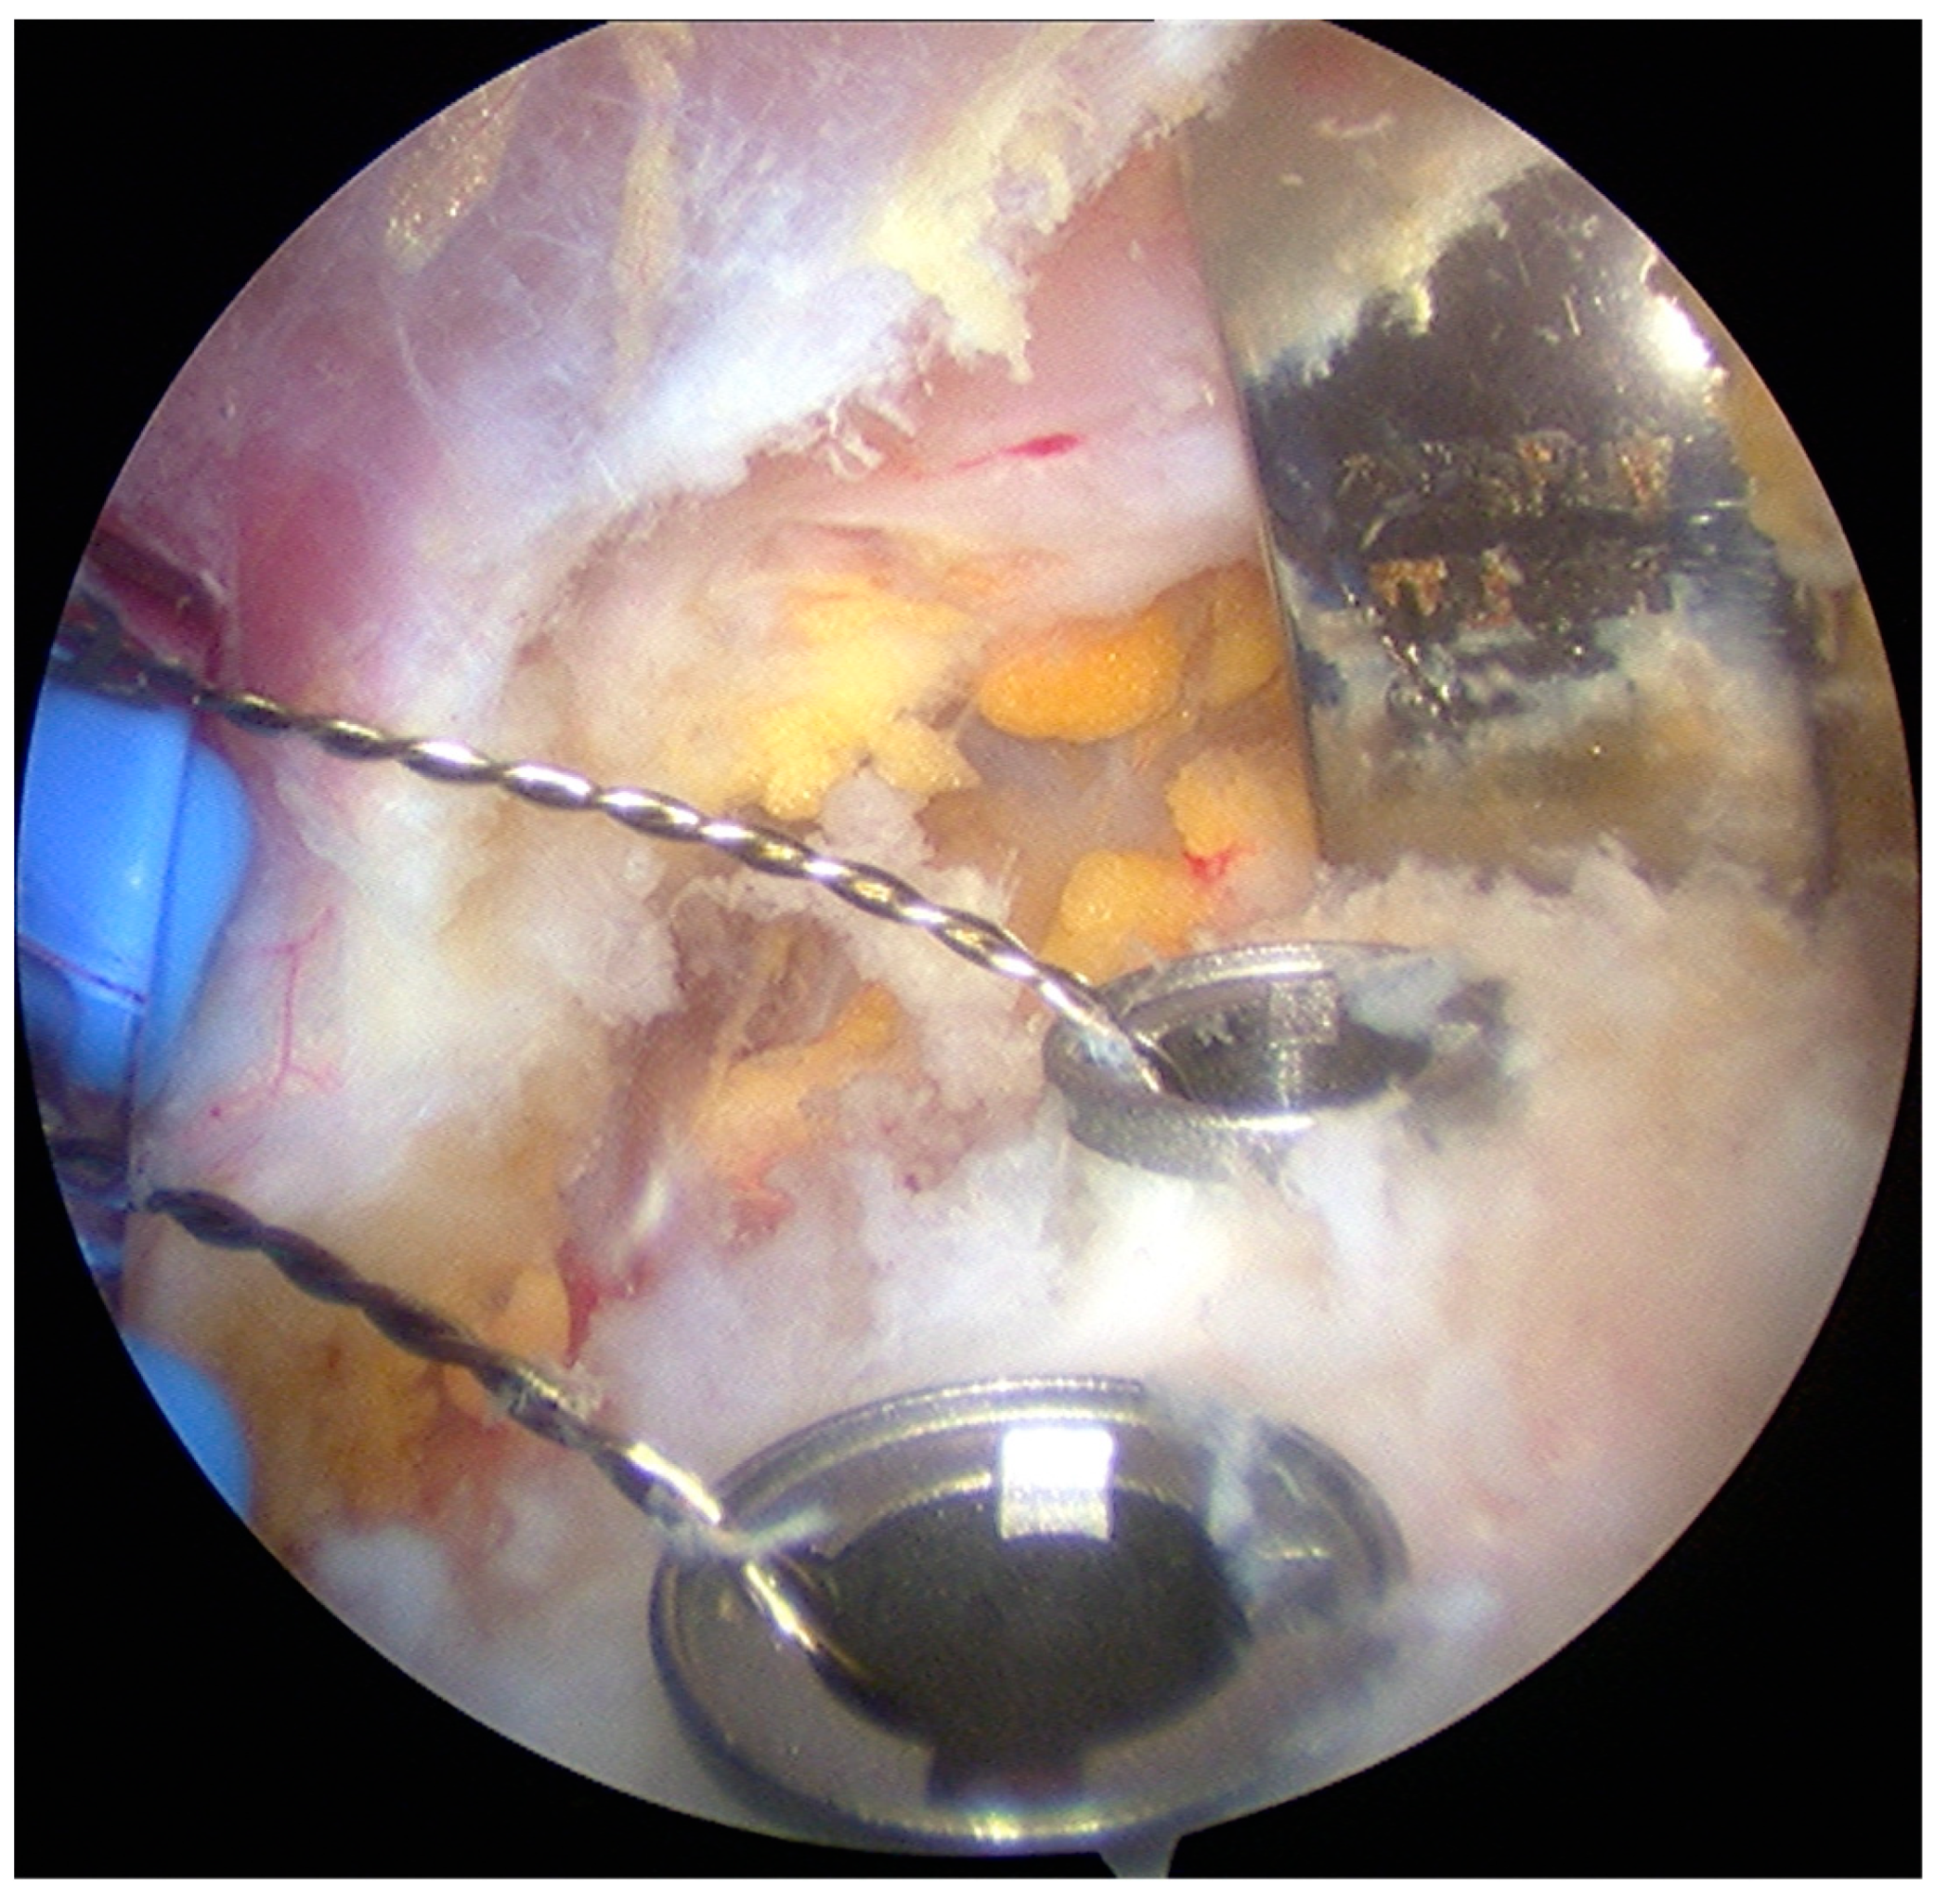

- The pectoralis minor was released, and a fresh portal was established with a needle over the coracoid, to insert the drill holes, at the junction of the lateral 2/3 and the medial 1/3. Two Kirschner wires through the coracoid were passed. The drill guide was removed. The holes were tapped, and the top hats were inserted into the fragment using a flexible Chia wire. The osteotomy was completed (Figure 2). The bone fragment was secured thought a coracoid screw passed over the Chia wire, using a double cannula.